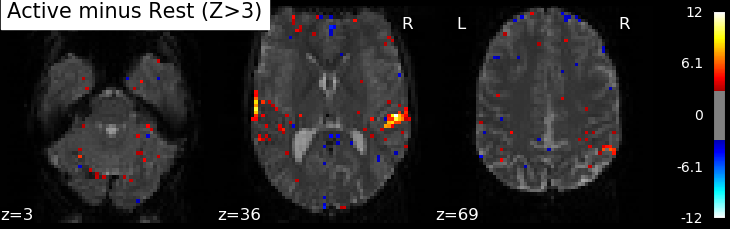

Correlations are computed separately at each voxel and a correlation map can be produced displaying the values of correlations (real numbers between -1 and +1) at each voxel. Generally, however, the maps presented in the papers report the significance of the correlations at each voxel, using T, Z or p values for the null hypothesis test of no correlation (see below). For example, the following figure displays a Z-map showing voxels responding to auditory events. Large (positive or negative) values are unlikely to be due to chance alone. The map is thresholded so that only voxels with a p-value less than 1/1000 are colored.